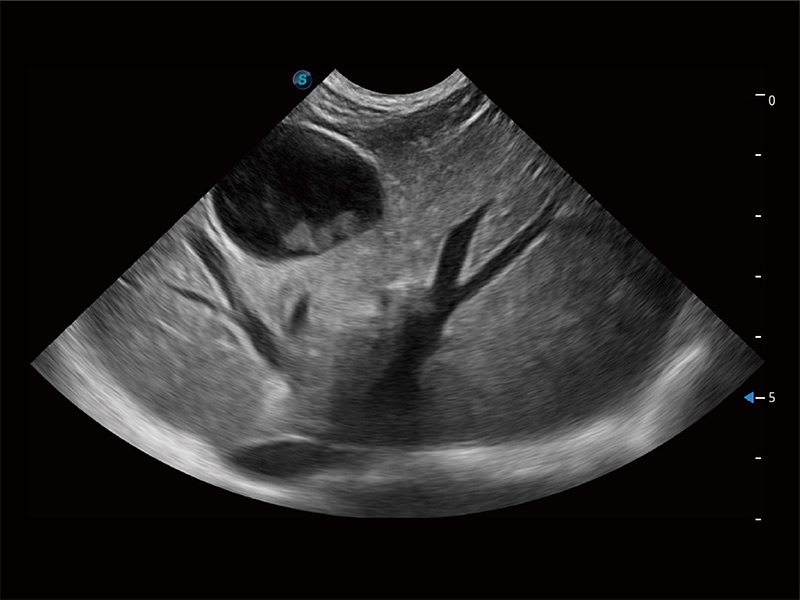

ProPet 80 配备了丰富的心脏探头群、先进的成像技术和专业的心脏测量工具,可帮助动物医生为不同体型和生理结构的动物提供心脏和心肌功能的全面评估。

能够增加心肌组织与血流之间的区别。对于心脏扫查困难的动物,可提供更好的心内膜边界的显示。